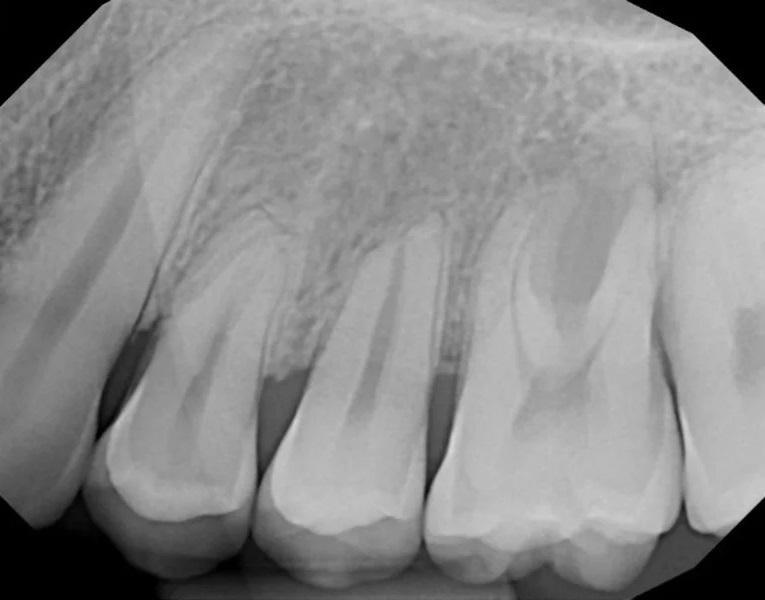

Фото 3. Предоперационный периапикальный рентгеновский снимок, показывающий короткие, затупленные корни зубов № 2.4, с апикальной резорбцией корня зуба № 2.5 и дистального щечного корня зуба № 2.6. Отмечалась тесная близость корней зубов №№ 2.6 и 2.7 с умеренным образованием интерпроксимальных кариозных полостей. Рентгенологическое просветление в основном затрагивало фуркацию зуба № 2.6.